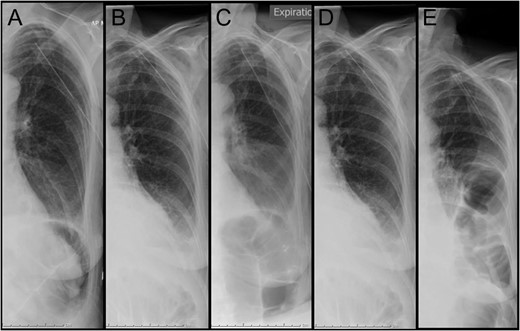

Daily chest x-ray documenting the left hemithorax. (A) Day 3 post admission: immediately post insertion of intercostal catheter. (B–D) consecutive chest x-ray on Days 4, 5 and 6 post admission. (E) Day 7 post admission: diagnostic of bowel loops in left hemithorax.